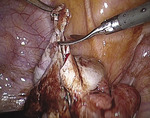

Delikatnie wsunięto pod lewy jajnik rurkę ssąco-płuczącą wprowadzoną przez lewy trokar. Następnie uniesiono przydatki lewe zrośnięte z blaszką tylną więzadła szerokiego. Po uwidocznieniu zrostu jajnika z otrzewną ruchem piłującym na tępo uwolniono zrosty narzędziem wprowadzonym przez przeciwległy port (ryc. 2). Podczas uwalniania zrostów z jajnika wylała się treść o barwie czekoladowej, którą odessano (ryc. 3). Po uwolnieniu zrostów („postawieniu” przydatków) i zbadaniu wnętrza torbieli zdecydowano się na zabieg oszczędzający (wyłuszczenie torbieli).